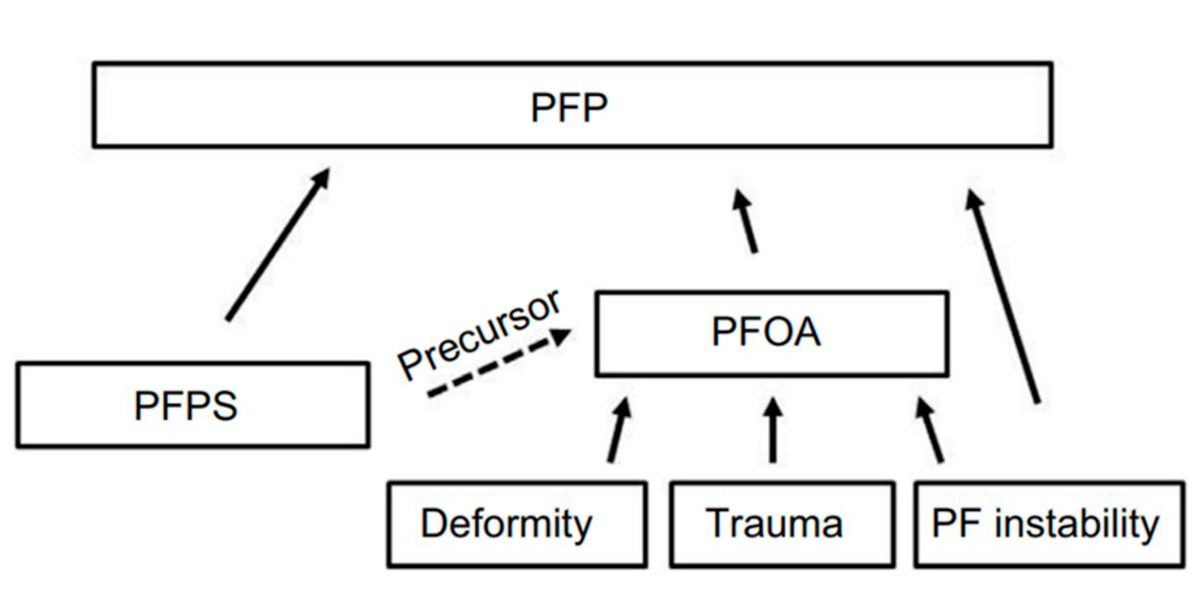

Síndrome de dor patelofemural

É isto que acontece com os jovens que sofrem desta sintomatologia, e é aquilo que denominamos de dor patelofemural.

Figura III. Chart Flow do desenvolvimento da dor patelofemural.

É importante o seu diagnóstico e saber como lhe reagir de imediato antes de causar danos estruturais na articulação, uma vez que é um problema que afeta 25% dos praticantes de desporto diagnosticados com este síndrome e que deixam de praticar exercício físico.